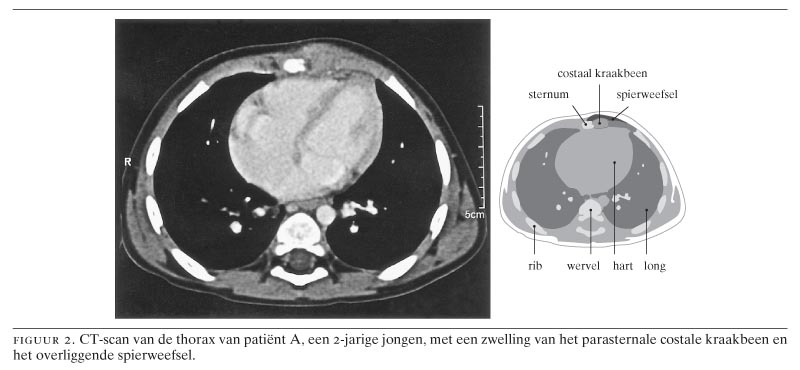

Wat is het precies? Nou, denk aan je ribben. Die zitten vast aan je borstbeen met kraakbeen. Klinkt logisch, toch? Nou, bij het Syndroom van Tietze raakt dat kraakbeen ontstoken. Aauw!

Maar wacht even, het is niet hetzelfde als Costochondritis, hoor! Ja, ik weet het, nog een fancy woord. Costochondritis is ook een ontsteking van het kraakbeen rond je ribben, maar... tromgeroffel... het Syndroom van Tietze gaat vaak gepaard met zwelling. Dus, rood, dik, pijnlijk... de hele mikmak. Costochondritis is meer de sneaky, stille variant. Begrijp je het nog?

Zwelling: Zoals we al zeiden, dit is het verschil met Costochondritis. Je borstbeen en de ribben eromheen kunnen opzwellen en rood worden. Ziet er niet gezellig uit.